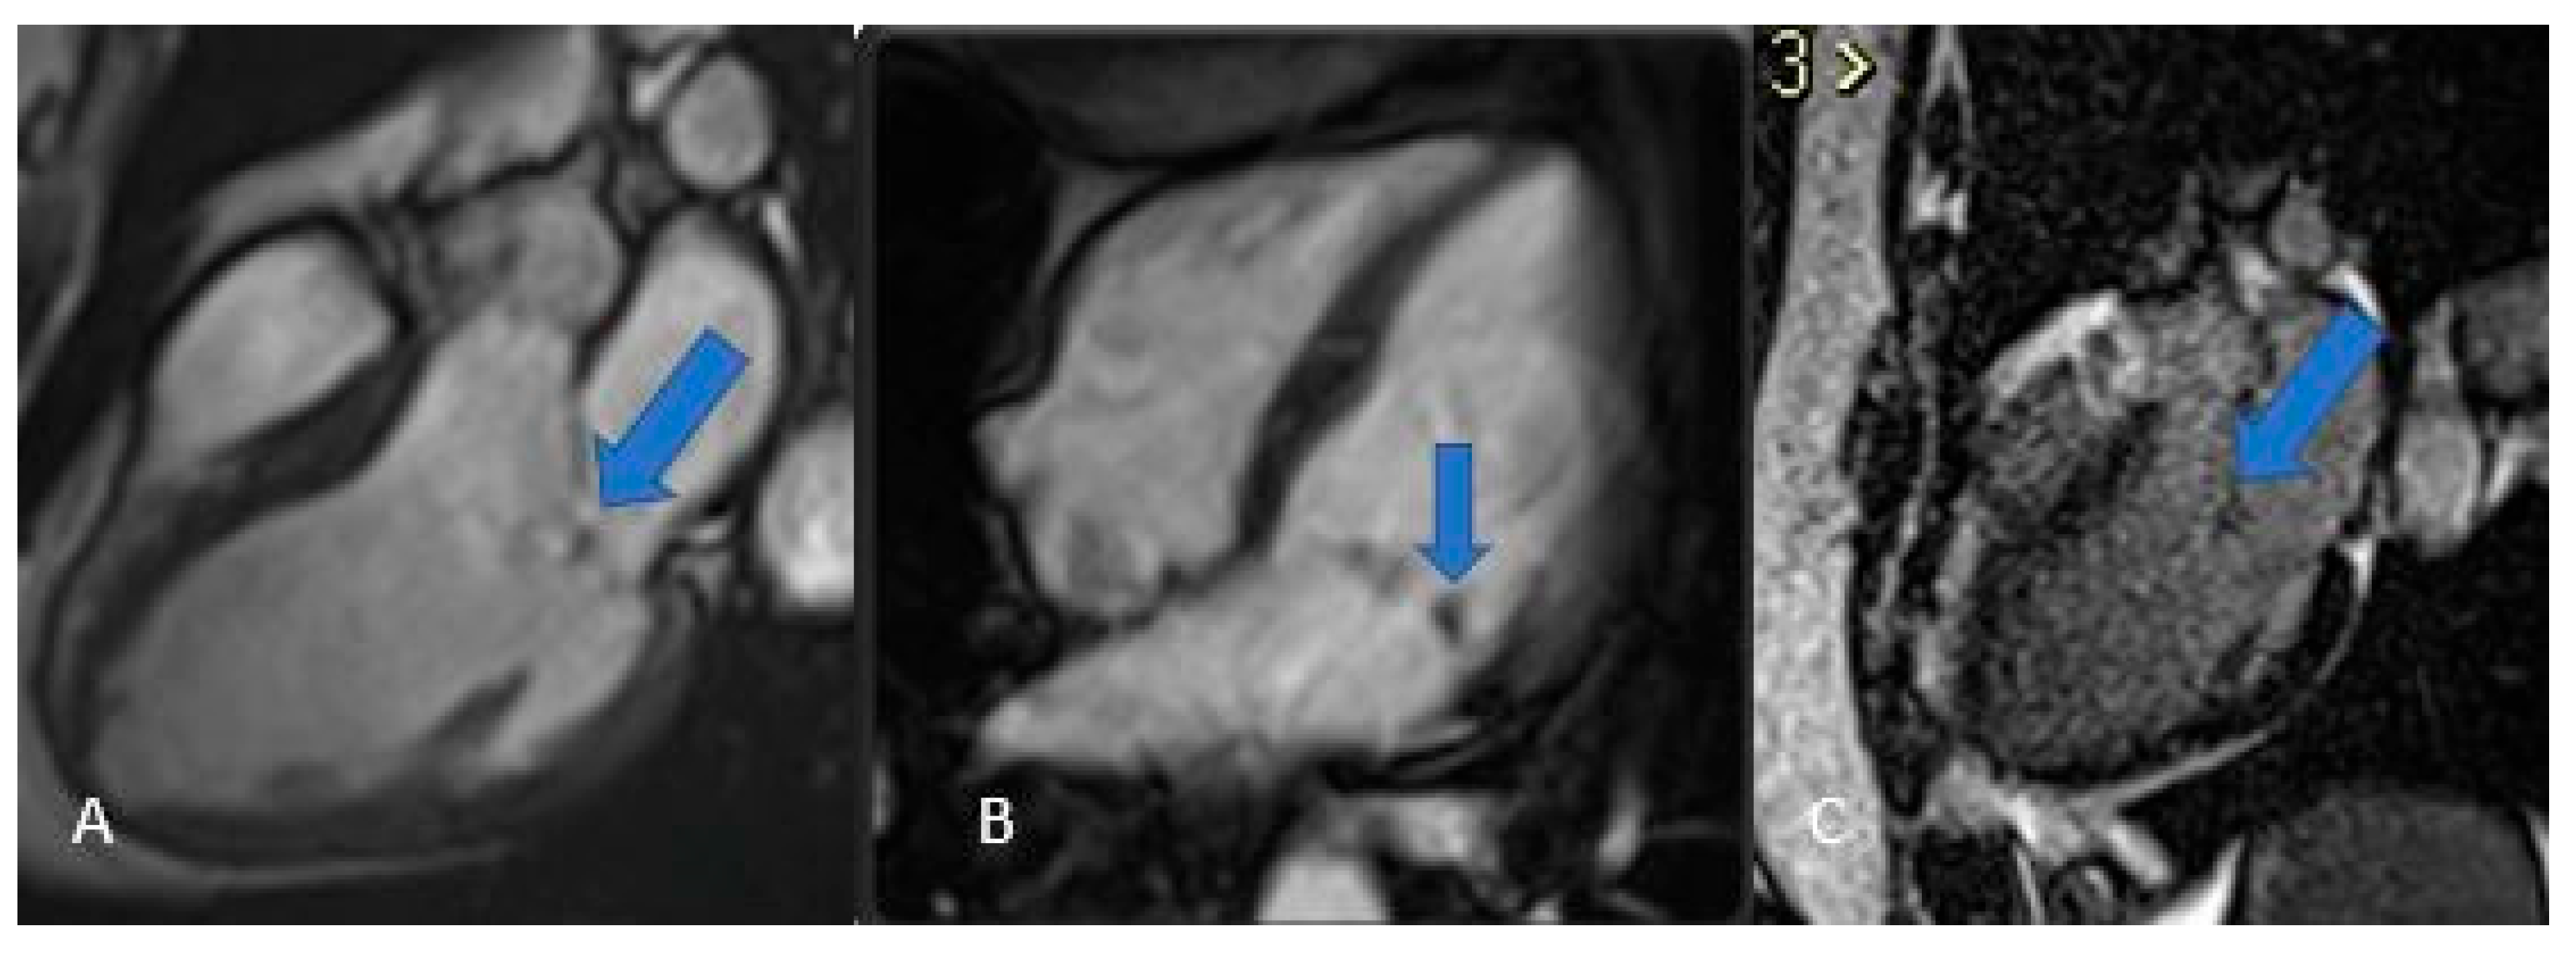

Figure 13. Angiosarcoma (arrows). Note the heterogeneous contrast enhancement and the slightly brighter appearance in T2 (C) compared to T1 (A and B). These features are indicative of the aggressive nature of angiosarcomas and aid in differentiating them from benign lesions. In perfusion (D) it shows no uptake.

Cardiac angiosarcoma (Figure 11 and Figure 12) is the most common malignant tumor of the adult heart. Patients usually present with symptoms and signs of heart failure or cardiac tamponade. These tumors typically originate from the right atrium and extend to the pericardium. There are two morphological types of sarcoma:

• Well-defined mass: Protrudes into the cardiac chamber, appears on CT as a hypodense mass with irregular or nodular margins, usually originating from the free wall of the right atrium, and shows heterogeneous contrast uptake.

• Diffuse infiltrative mass: Extends towards the pericardium, which can be obliterated by necrotic or hemorrhagic tumor. The prognosis is unfavorable because the pathology is usually asymptomatic until advanced and often metastatic [3,22,27].

Histologically, angiosarcomas exhibit sheets of highly proliferative, anaplastic endothelial cells that invade perivascular spaces in a disorganized fashion, leading to frequent hemorrhage and necrosis; on MRI they appear heterogeneously signal-intense on both T1- and T2-weighted images, with irregular contrast uptake and patchy late gadolinium enhancement corresponding to fibrotic islands [27].